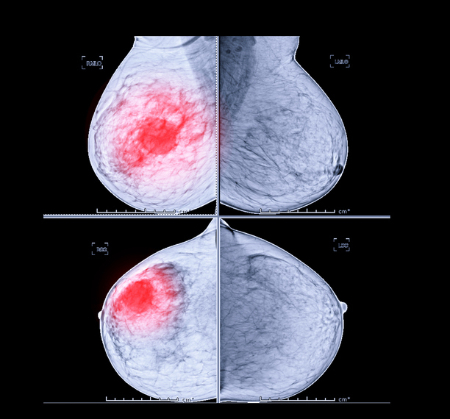

한국보건의료연구원, 침윤성 유방암 4130명 분석

이에 PACEN은 유방암을 보는 전문가들과 함께 '초기 유방암 환자에서 추적 관찰검사법의 최적화 연구'를 시행했다. 서울대병원 문형곤 교수를 연구 책임자로 선정하고 PACEN의 지원으로 2010~2011년 국내 12개 대학병원에서 유방절제술을 받은 침윤성 유방암 환자 4130명의 데이터를 분석했다.

그 결과, 유방암 수술 후 추적관찰 영상 검사(CT, 뼈 스캔 등)를 고강도로 수행한 환자군(고강도 검사군)이 저강도 검사군에 비해 원격 전이를 더 빨리 발견했다. 고강도와 저강도의 기준은 전체 검사 횟수 평균치보다 높은지 등을 참고했다. 다만, 두 군의 유방암 특이 생존율은 유의미한 차이가 없는 것으로 파악됐다. 유방암 수술 후 고강도 추적관찰 영상 검사가 전이 발견에는 유리하지만, 생존율 개선과는 직접적인 연관이 없다는 점을 시사하는 결과다.